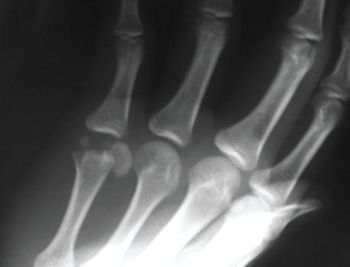

An 18-year-old complained of pain and decreased mobility of the small finger in his right hand after a softballinjury. While sliding back to second base during a pickoff attempt, the patient hit his hand on the bag.

A 63-year-old woman presented with a 2-year history of bilateral hand pain and stiffness that had worsened in recent months. The pain was most severe in the fingers and was associated with morning stiffness that lasted 30 minutes. There was loss of full range of motion in some finger joints.

A 51-year-old African American man with a 15-year history of chronic hepatitis C and sarcoidosis presented with persistent bilateral hand pain. The pain was aggravated by physical activity and had a waxing-and-waning pattern.